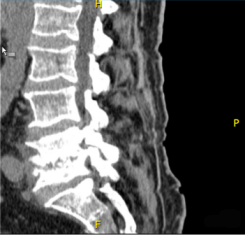

- Σύρετε τον δείκτη του ποντικιού για να μετακινήσετε τον μεγεθυντικό φακό σε διάφορα σημεία της εικόνας τα οποία θέλετε να δείτε.